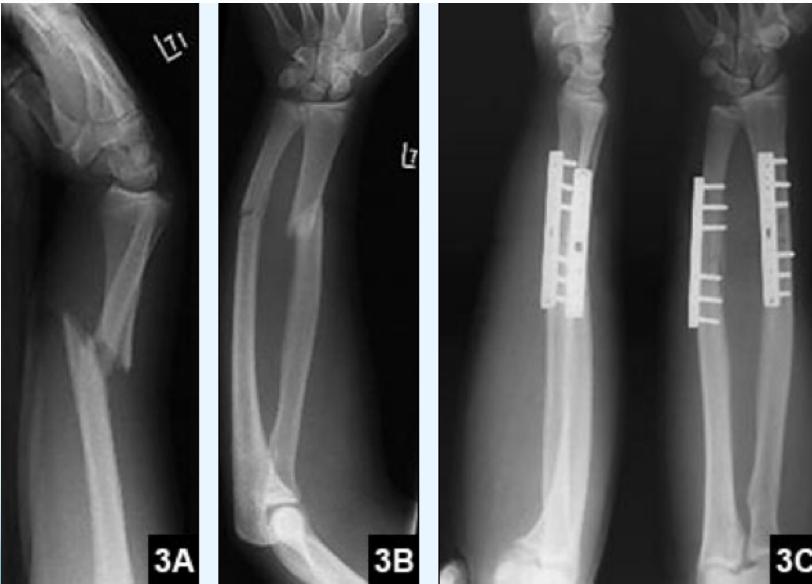

- When ORIF: plating

Age consideration: 14-15 years old - may need plating

Teddy Slongo, Bern, Switzerland

Plating